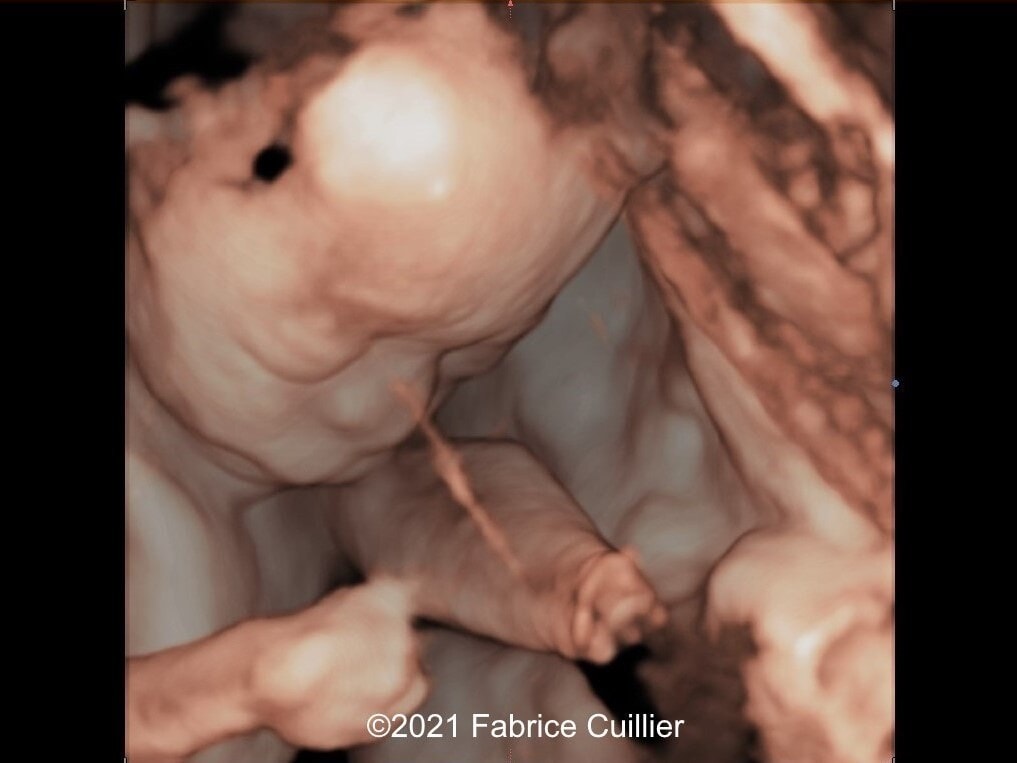

• Images 8,9: Ultrasound at 23 weeks gestation showing an amniotic band near the external right ear causing a stricture on 3D image.

We considered fetal surgery to release the amniotic bands and alleviate the strictured tissues, however at 24 weeks gestation there was fetal demise. External examination of the fetus confirmed the left foot edema and stricture of the left leg soft tissue. Additionally, there was amputation of several fingers of the right hand that was missed on prenatal ultrasound (Image 4).